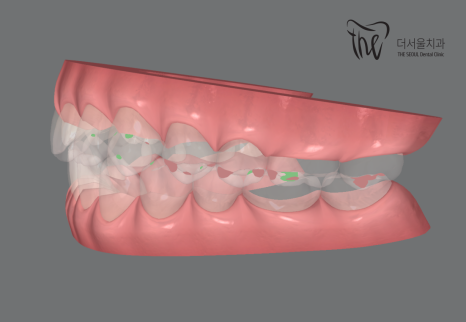

『인비절라인 클린첵 시뮬레이션』

클린첵 시뮬레이션을 응용하면,

여러가지 결과들을 시각화 해서 볼 수 있습니다.

육안검진으로는, 절대 뒤쪽에서 앞쪽을

바라보면서 진단을 내릴 수 없죠.

이렇게 3D로 구현을 해서, 한 눈에

현재 상황을 판단 할 수 있게 도와줍니다.

그러면서, 치아들끼리 어디가 맞물리는지를

볼 수 있는데 이런 데이터들을 바탕으로

어태치먼트들의 형태나 모양을 설계하며,

어떤 식으로 치열 변화를 일으켜야 좋은 결과를

가져다 줄 수 있는지를 볼 수 있습니다.^^